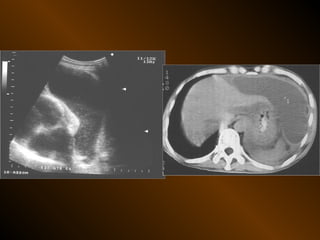

TỤ DỊCH TRONG PHÚC MẠC

• X QUANG QUY ƯỚC

– Trong tiểu khung

– Dọc hai bên hông

– Giữa bụng

• SIÊU ÂM

– Phản âm trống, chuyển dịch

– Lượng ít

– Bản chất dịch

• X QUANG CẮT LỚP ĐIỆN TOÁN

– Mật độ

– Vị trí

– Nguyên nhân

TỤ DỊCH KHU TRÚ

– Tụ dịch ? – khối u ?

– Phản âm, chất chứa, vỏ bọc ?

– Mật độ, bắt cản quang ?